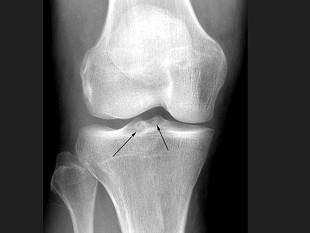

问题 女,65岁,右膝痛,活动受限,结合图像,最可能的诊断是?(?)

选项 A.神经性关节病 B.创伤性关节炎 C.退行性骨关节病 D.类风湿关节炎 E.痛风

答案 C